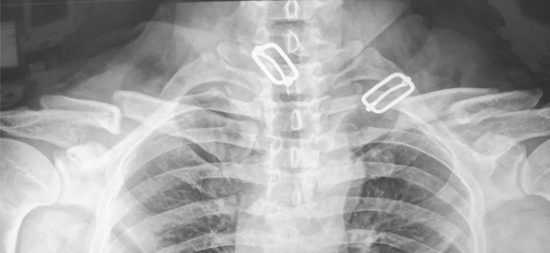

▲双侧锁骨骨折,移位明显